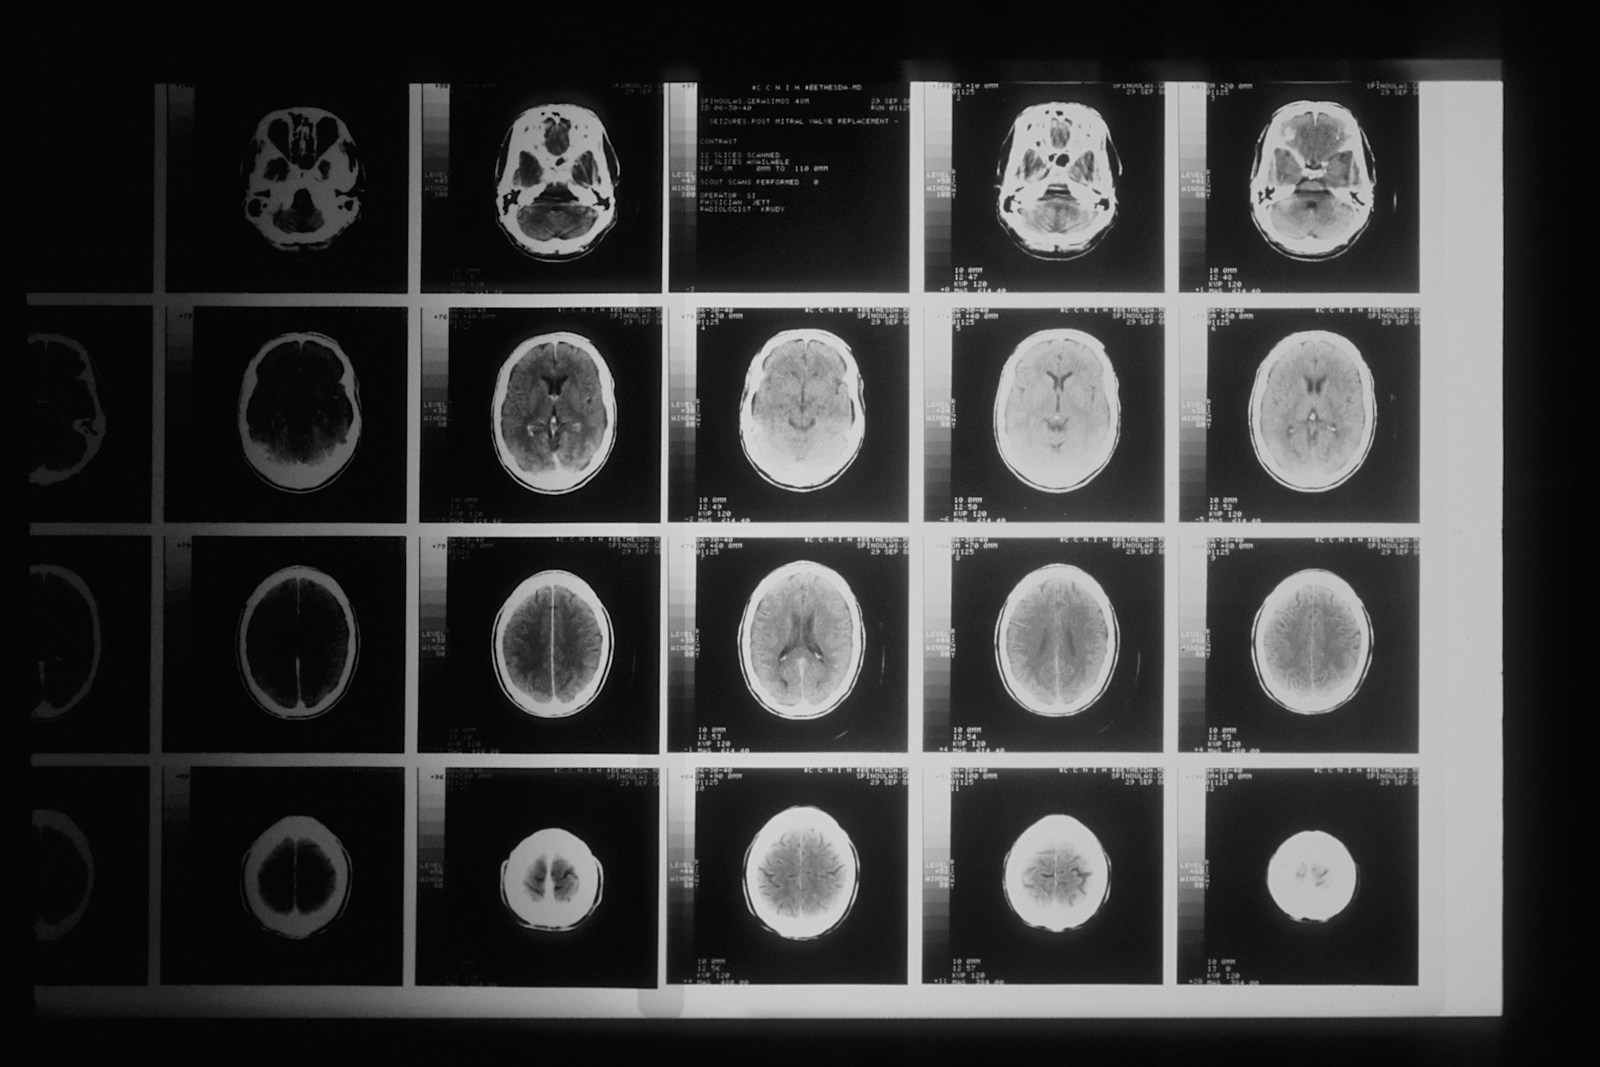

AI-powered diagnostic imaging